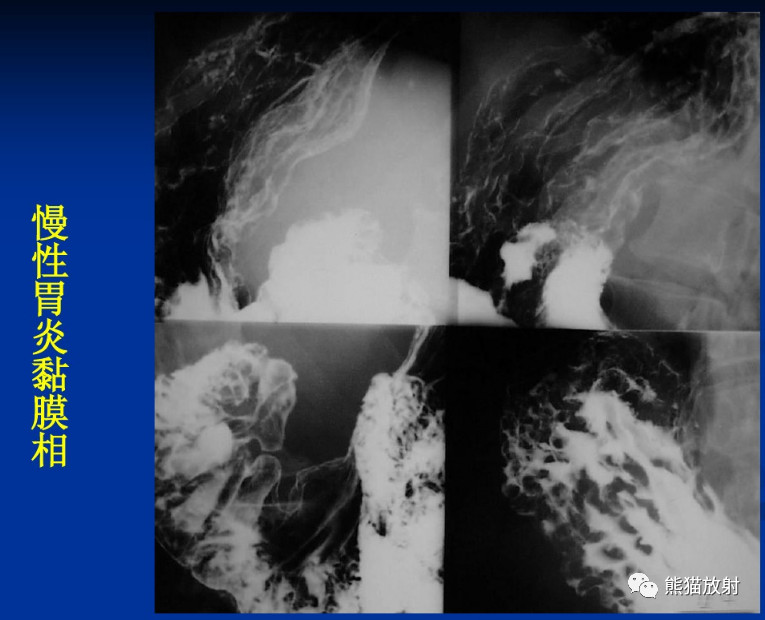

X线表现:过去通常将慢性胃炎分为浅表性、肥厚性和萎缩性。表现如下:

(1)慢性浅表性胃炎:常无明显异常X线表现。可见胃窦及体部局限性不规则挛缩波,黏膜纹略粗、紊乱,有时可见浅表小溃疡,局部压痛,壁柔软。

(2)慢性萎缩性胃炎:黏膜纹常纤细、稀少或消失,呈光滑无凸征象(特别是气钡双重造影有价值),黏膜沟增宽,大于5mm,有时也可见局限性挛缩波,胃张力低。

(3)慢性肥厚性胃炎:黏膜纹隆起、粗大而宽、排列紊乱、扭曲不整,皱襞数量减少、表面粗糙,常有多发表浅小溃疡及大小不等的息肉样结节。本病多发生于胃窦,常致功能挛缩狭窄。胃内有滞留液。可见胃壁柔软及黏膜纹可塑性,无破坏中断。常伴胃黏膜脱垂及十二指肠球炎和溃疡。气钡双重造影可见胃小区增大。